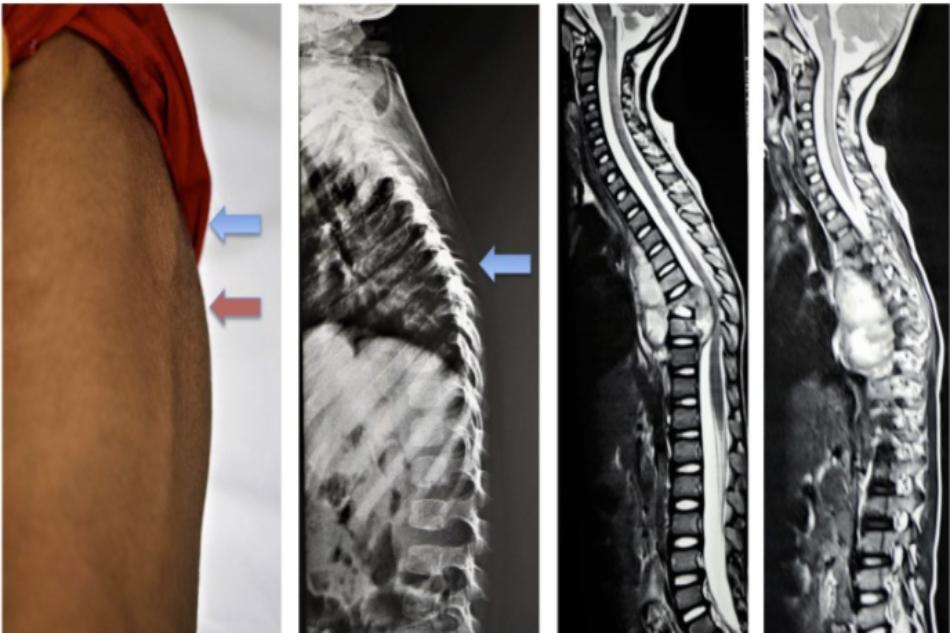

Bài viết TỔN THƯƠNG THÂN ĐỐT SỐNG, ĐĨA ĐỆM DO LAO – Tải file PDF Tại đây. Nguồn: Viện/Trung tâm/Khoa: Chấn thương chỉnh hình và cột sống – Bệnh viện Bạch Mai ĐỊNH NGHĨA Tổn thương thân đốt sống, đĩa đệm do lao (lao cột sống) là tình trạng nhiễm khuẩn đốt sống và đĩa… Xem thêm

1. Bệnh lý Lao cột sống là gì? Là bệnh lý tổn thương đốt sống do vi khuẩn lao ( Mycobacteri Tuberculosis). Còn gặp nhiều ở các nước đang phát triển, chiếm khoảng 50% – 60% các trường hợp lao xương khớp. Tổn thương ở đoạn cột sống ngực và thắt lưng chiếm hơn 90%…. Xem thêm